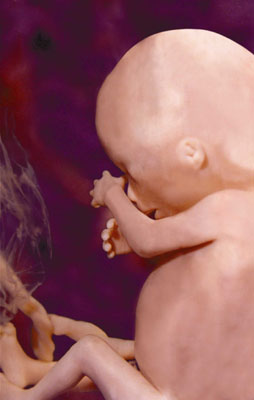

this is what an unborn baby looks like at 20 weeks (five months)

Offers of financial help, free housing, and offers to adopt the babies poured in as soon as this picture when viral. Unfortunately, despite so many people’s prayers and offers of help, this woman aborted her baby girls. See a picture of what babies look like at 20 weeks after they are aborted